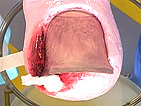

[IMG]30.09.2010-3-pre.jpg2017-04-25 08:59 33K